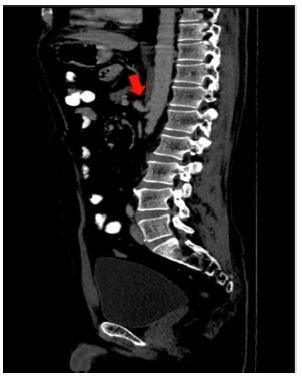

E.g., MALS i.e., Median arcuate ligament syndrome (Dunbar syndrome). The median arcuate ligament is a fibrous arch uniting the diaphragmatic crura at the level of the aortic hiatus and passes superior to the coeliac artery origin. However, if the insertion is low, it can cause abdominal pain. The diagnosis of coeliac axis compression / median arcuate ligament syndrome / Dunbar syndrome is done with conventional angiography/ CT angiography. The CECT imaging findings are characteristic focal narrowing in the proximal coeliac axis with a characteristic juxta-ostial hooked appearance with coeliac artery origin stenosis (Figure 7)[2].

Figure 7: Sagittal CT reformats showing juxta ostial fishhook configuration of the coeliac artery with narrowing of the coeliac artery near the origin (Red arrow).